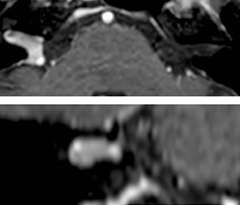

This is an example of acute ischemic stroke with distal occlusion of the right posterior cerebral artery. Note the improved visibility of the ischemic territory on the diffusion weighted image with high b-value. The 3D FLAIR shows a distal PCA occlusion. The fast SWIp depicts the thrombus on the isolated second echo image. The total scan time (including SmartBrain, preparations and a fast 3D T1w TSE Gd) is 8:00 minutes.

Dr. Savatovsky appreciates the improvements and flexibility that Elition with Compressed SENSE and MultiBand SENSE provides, particularly for stroke patients. “For stroke, it allows us to cut about 5 minutes off of our stroke protocol, or to keep the same acquisition time and get more insights.” The ability to perform more sequences can help in making a swift and confident diagnosis. “For example, our stroke cases usually include the regular sequences that every center does (b1000 diffusion, FLAIR, time-of-flight angiography), but we also image supra aortic vessels, and we can replace a gradient echo sequence with a fast 50-second susceptibility-weighted sequence, and all of this doesn’t add much time. because all the regular sequences are accelerated on Elition.” “The time savings with Compressed SENSE and MultiBand SENSE make it easier to add sequences to give us additional insights. Depending on the context and the first results, we might add a DSC perfusion to assess the ischemic penumbra, an ASL perfusion to help find an alternative cause in case of normal diffusion, or add a high-resolution T1 sequence for a stroke patient, to quickly assess wall imaging in emergency cases. The additional sequences can help improve patient management, because we can already consider some alternative diagnoses if the morphological MRI is normal.”

Using MultiBand SENSE allowed the staff to improve their diffusion quality. “Our diffusion sequence was already fast before, about 40 seconds. Now with Elition, it still lasts 40 seconds, but we improved the spatial resolution by 0.2 mm and use high b-values to be more sensitive to visualize changes related to acute stroke,” says Dr. Savatovsky. “We now also developed a high resolution DTI sequence (1.3 x 1.3 x 2 mm) that can be reformatted and takes 2 to 5 minutes depending on the coverage. We use it every time we have a doubt, or when we expect the diffusion to be abnormal but don’t see that on the fast sequence. We occasionally spot small ischemic infarctions that would not have been visible with the regular diffusion sequence.”